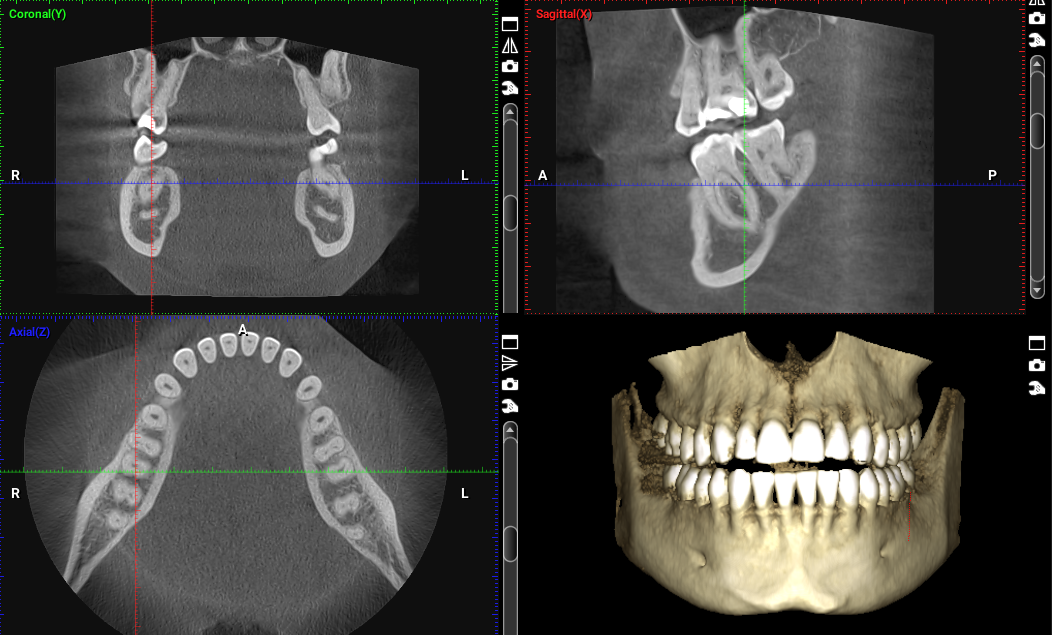

In the most complex cases, we can do 3D CT scans  without any delay as we have the very latest CT scanner at the practice

You may need to have X-rays taken of your mouth and teeth to rule out other conditions, such as a bone infection (osteomyelitis) or small fragments of root or bone remaining in the wound after surgery.